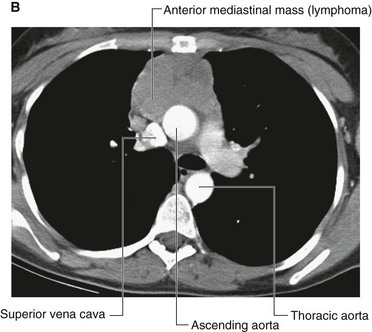

Lymph nodes may become diffusely enlarged in certain systemic illnesses (for example, viral infection), or local groups may become enlarged with primary lymph node malignancies, such as lymphoma (Fig. 1.32).

image image

Fig. 1.32 A. This computed tomogram with contrast, in the axial plane, demonstrates the normal common carotid arteries and internal jugular veins with numerous other nonenhancing nodules that represent lymph nodes in a patient with lymphoma. B. This computed tomogram with contrast, in the axial plane, demonstrates a large anterior soft-tissue mediastinal mass that represents a lymphoma.